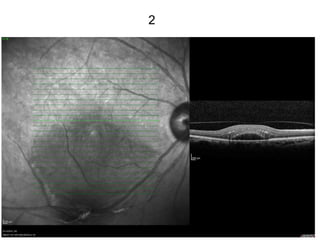

2

98

99